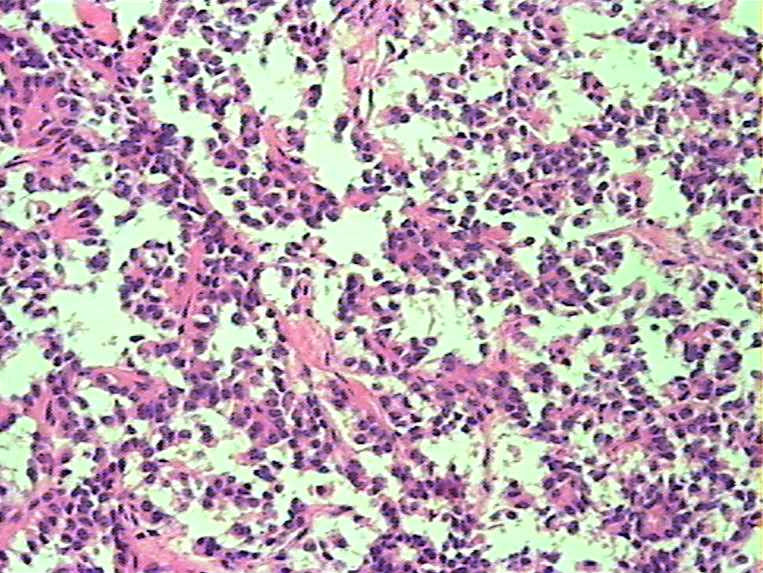

胰腺肿物 大体:灰白色肿物一枚大小:3*2*2cm,切面实性,质中。女,52

• 胰腺肿瘤图3

图3

胰腺实性-假乳头状瘤

实性假乳头状瘤

胰腺实性-假乳头状肿瘤(低级别恶性肿瘤)

会诊实性假乳头状瘤

胰腺实性-假乳头状肿瘤

胰腺实性假乳头状瘤